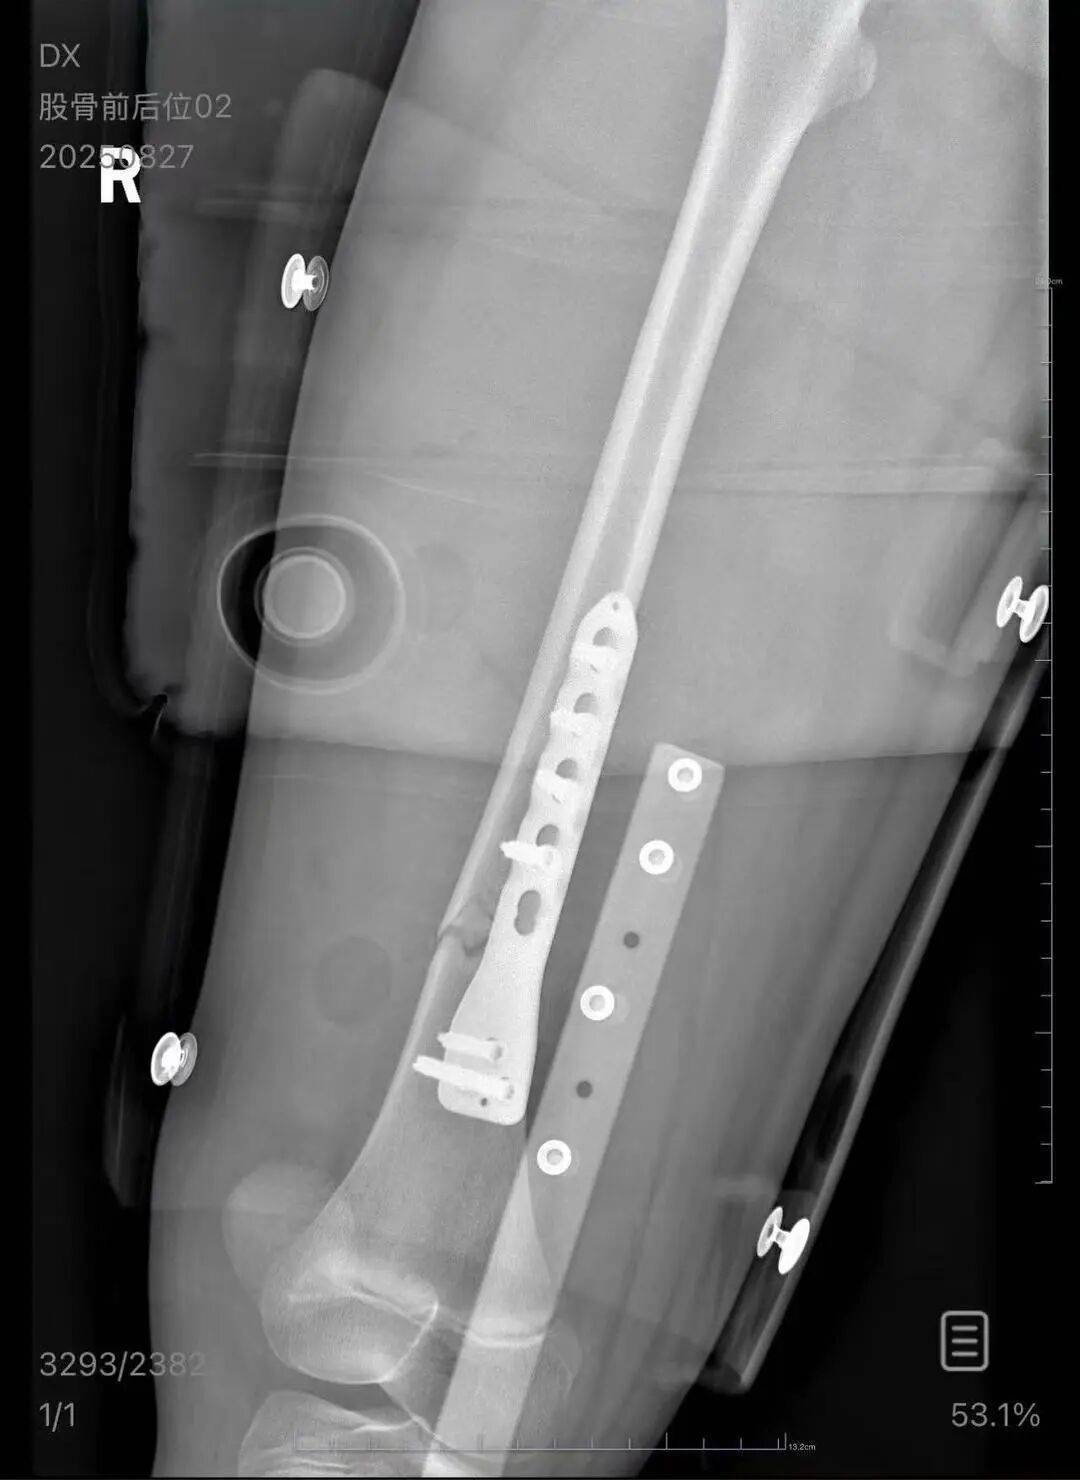

▲朱女士女儿手术后拍的X光片 受访者供图

朱女士向记者出示的医院病历显示,8月24日凌晨,朱女士的女儿到医院就诊tp钱包官网下载。医院诊断朱女士的女儿右股骨骨折,需要住院进一步治疗。

朱女士称,自己是离异状态,为了照顾小孩请假在家,也没有经济来源tp钱包官网下载。“现在孩子的医药费用已经花了5万多,后期还要进行康复治疗,我的压力非常大。”“医生说孩子还小,恢复快,钢板固定后很难恢复如初,甚至可能会出现长短腿的现象。”